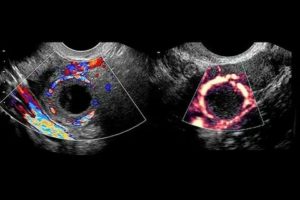

Как выглядит желтое тело на изображениях УЗИ

Описание лютеиновой железы на УЗИ:

Параметры Эхопризнаки Как выглядит

Внешний вид Гетерогенное анэхогенное образование На яичнике округлое темно-серое пятно с черными вкраплениями и единичными белыми точками

Структура Гиперэхогенное образование с крупными зонами низкой плотности (гипо- или анэхогенными очагами) Серое пятно с большой площадью затемнений. Окрашены черным места скопления крови, локализации сосудов

Размер В норме до 30 мм, при образовании кисты – более 3 см Диаметр ЖТ сверяют с нормой по фазам желтого тела

Если диагност выявил два желтых тела или больше, в протоколе УЗИ описывается каждое образование. Растущая и угасающая железа неодинаково выглядит. С началом регрессии она уменьшается, светлеет. Черное пятно без вкраплений – эхопризнак жидкостной кисты.